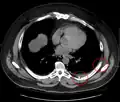

La fracture costale, rupture d'une ou plusieurs côtes, rend la respiration douloureuse, difficile. Elle peut entraîner une atteinte des poumons, et notamment un hémothorax (le poumon se remplit de sang) ou un pneumothorax (le poumon a une « fuite d'air » et ne peut plus jouer son rôle), qui peut mettre en jeu le pronostic vital.

• on ne visualise pas le parenchyme pulmonaire et donc les complications de la fracture costale que sont l'hémothorax et le pneumothorax[2], seul indication à un traitement ;